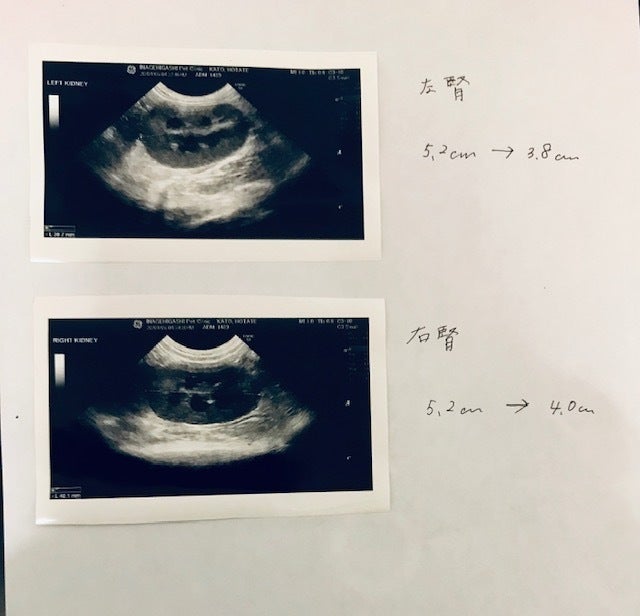

先日ずっと気になっていた腎臓の大きさの確認のため2ndオピニオン先の病院で超音波断層検査をして頂きました結果は画像の通りMUTIAN治療前の腎臓の様子とは全然違います大きさもそうですが、形、がほぼ正常に戻っています。本当に良かった!先日怪我した目の治り具合も見ていただき、こちらはもう傷も治り点眼必要ないと言われました!ほたては目薬だけは苦手みたいで終わってホッとしています。治療費は再診料込みの3300円ですまた、少し前に3ndオピニオン先で受けた血液検査(蛋白分画検査)の結果も報告いたします。大分数値的に良い数値になって来ています!この時は3/25に採血した結果なのでMUTIANを飲み始めて15日経過でしたここまで数字が変わってくれているのに感謝です。今月20日以降に再度血液検査を行います、行いましたらまた活動報告を上げさせていただきます。ほたて4/6の診察の時に体重が4.1kgになっていました!FIPの診断を受けた当初は3.6kgそこから少し減り強制給餌でなんとか減らないようにしていましたが今ではどんどん増えて行ってます喜ばしいのですが、お薬の量が増えるので私はドキドキです!現在は指示の下600mg飲ませています。まだまだ治療は続きますが、どうぞ皆さま変わらずほたてを温かい目で見守ってください。宜しくお願いいたします。